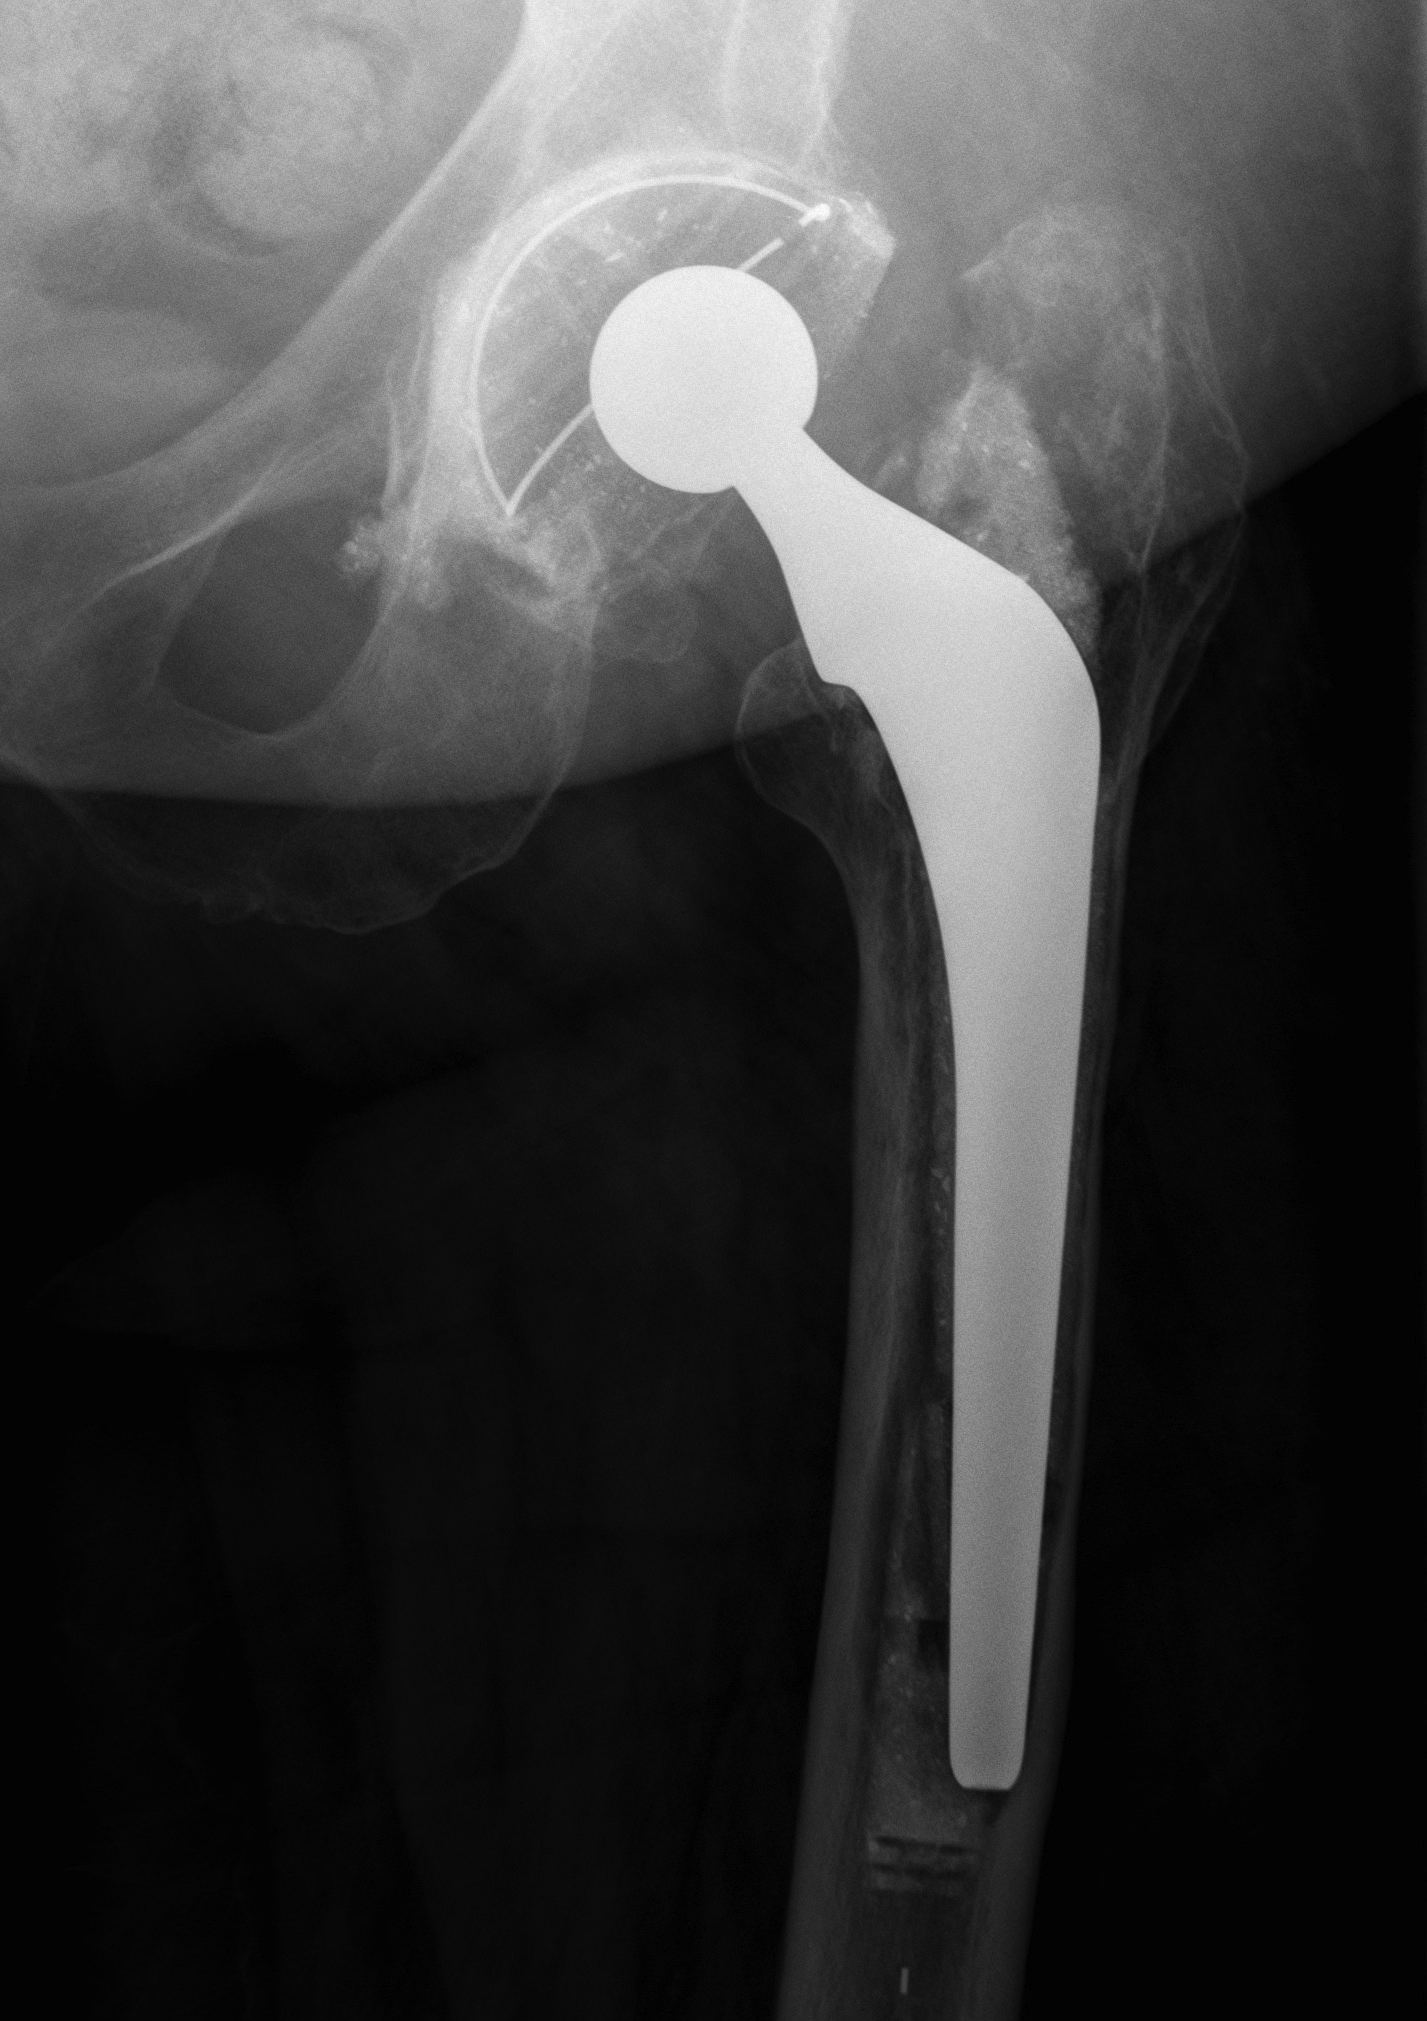

2. Extensively porous coated diaphyseal fitting uncemented stem

Indications

- Paprosky Types I, II, IIIA

Results

- 90- 95% 10 year survival

Problems

- fracture

- stress shielding with additional proximal bone loss